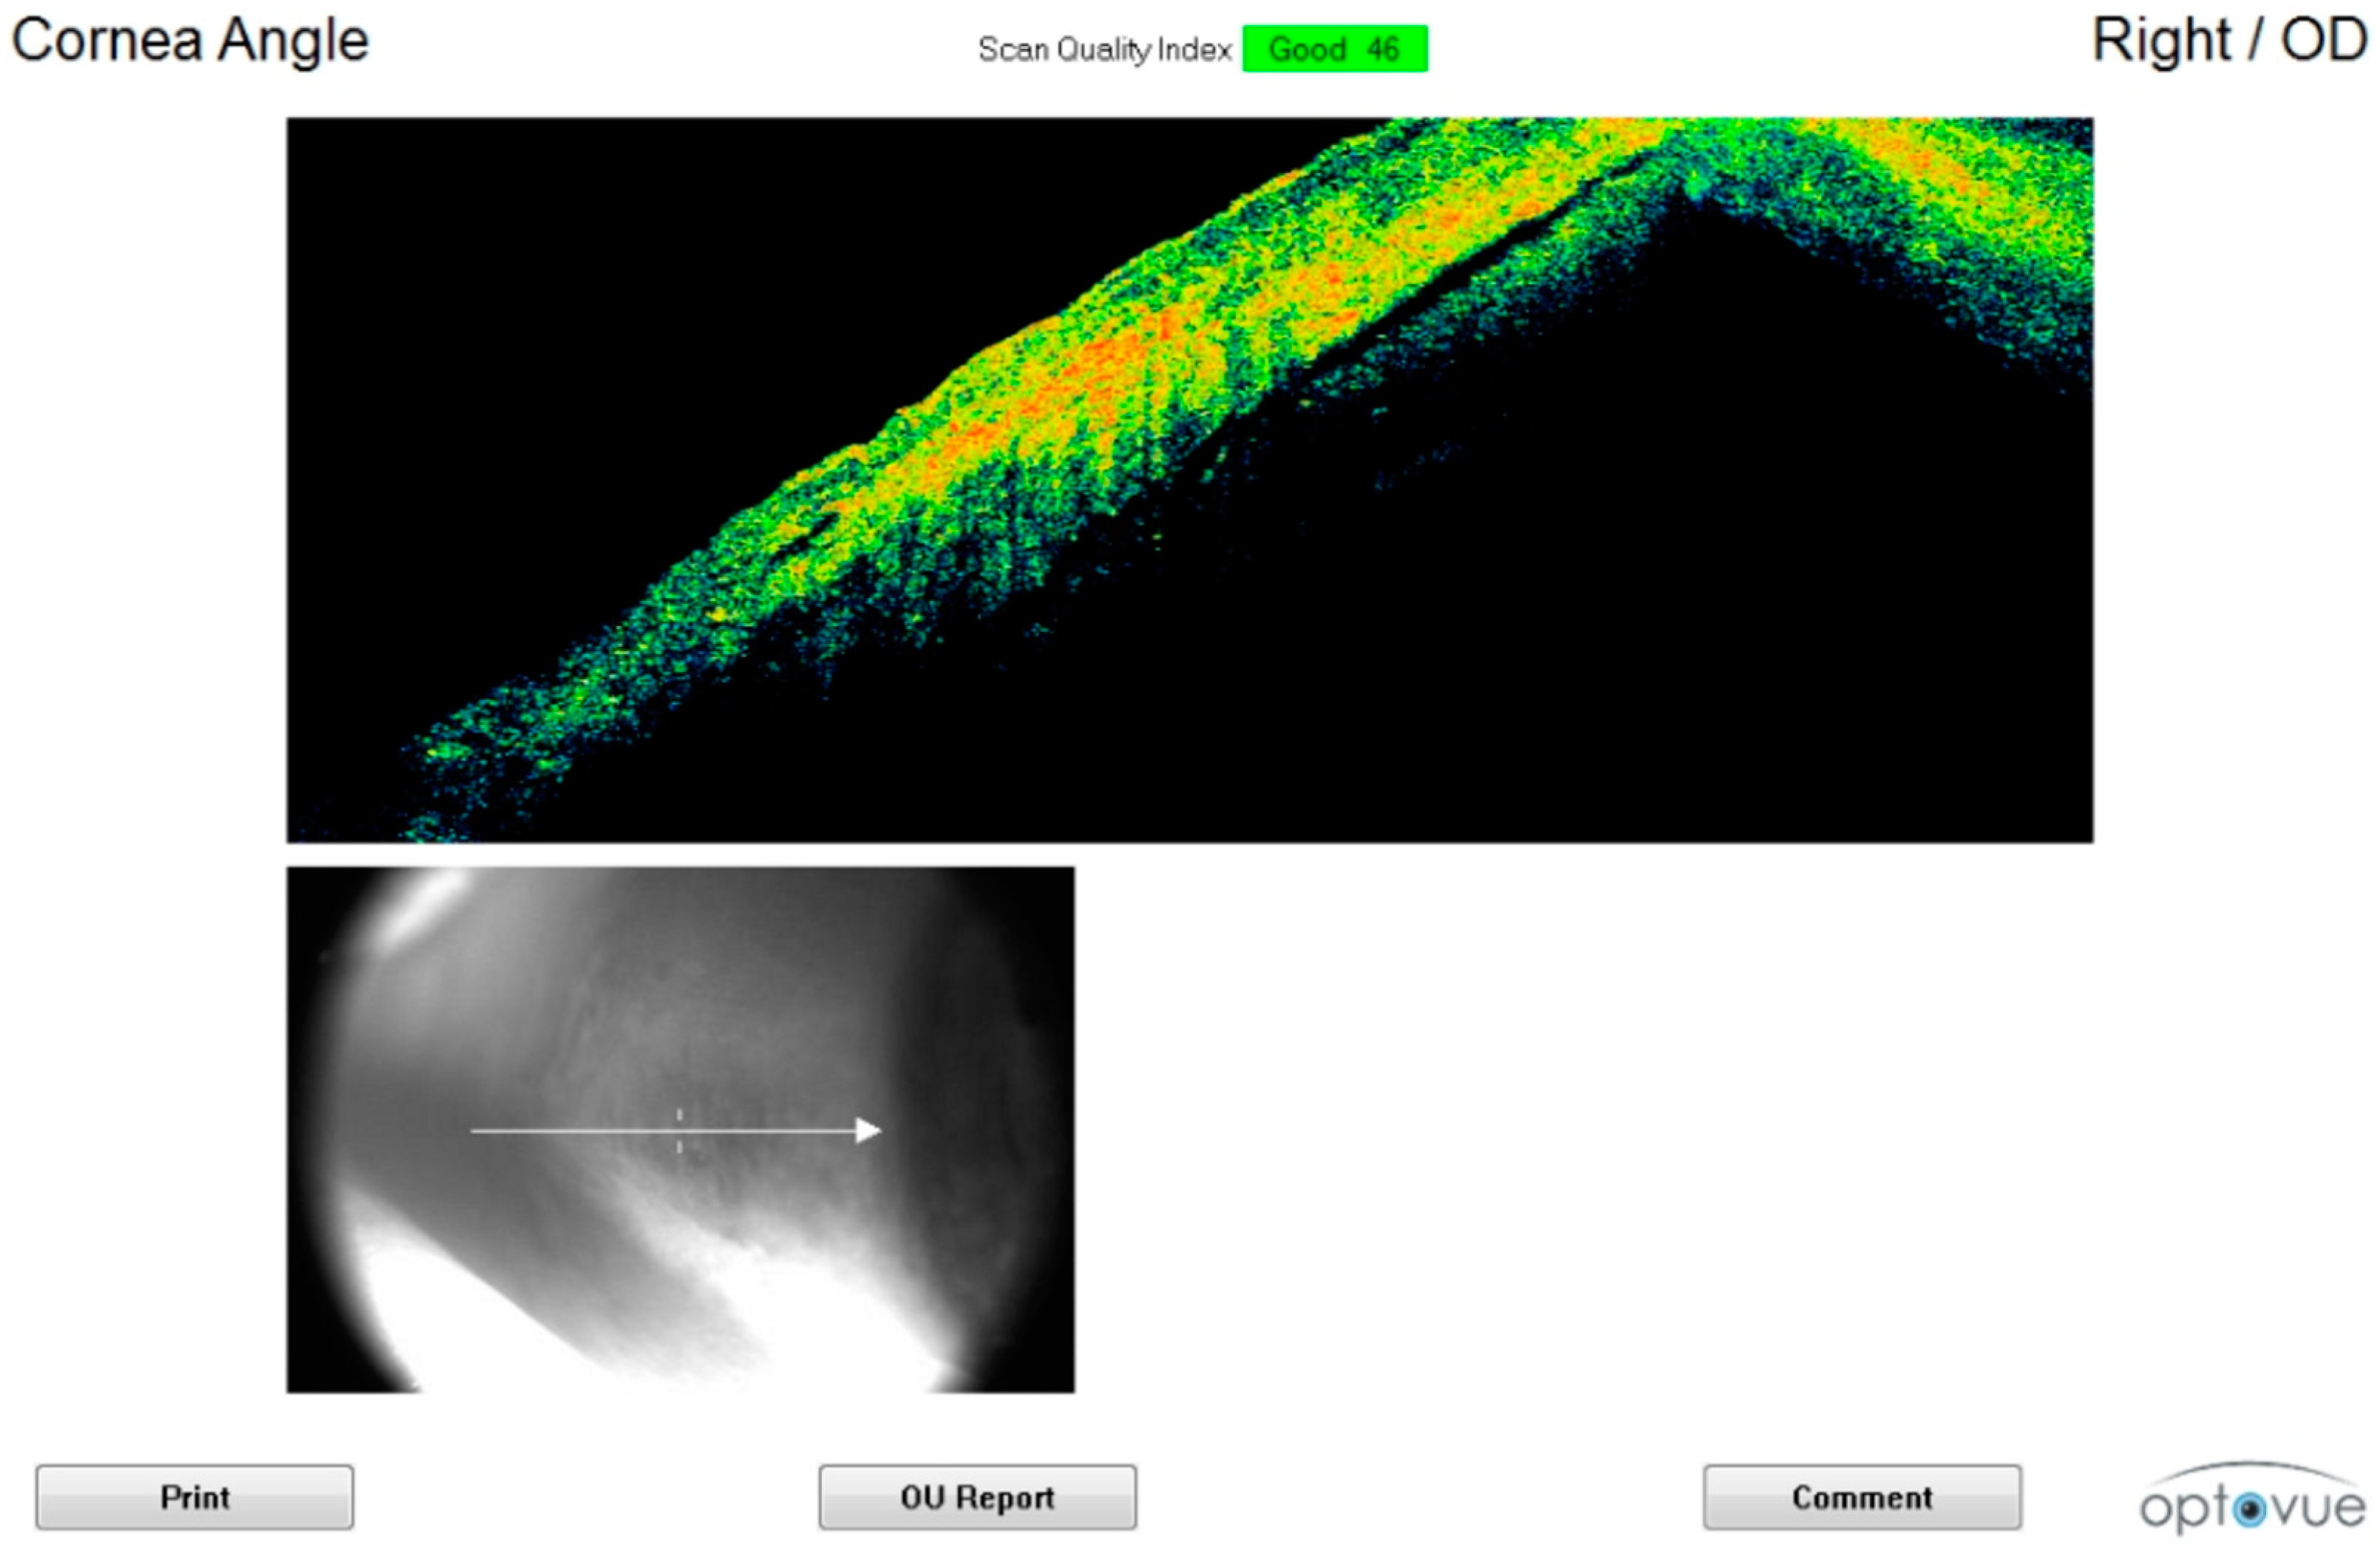

3.1. Cornea and Anterior Chamber